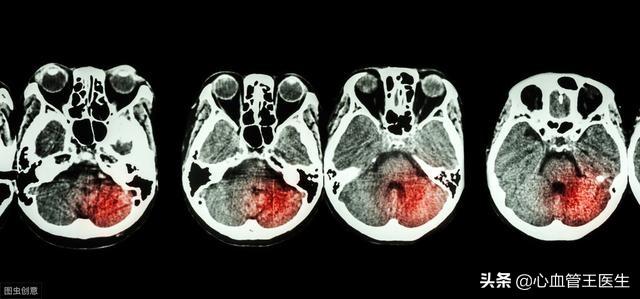

脳出血は、脳実質内の血管の非外傷性破裂による出血と定義され、脳卒中全体の20%から30%を占め、急性死亡率は30%から40%で、主に高血圧が発見されなかったり、高血圧のコントロールがうまくいかなかったりすることが原因である。

高血圧性脳出血は男性にやや多く、冬と春に起こりやすく、通常、活動中や感情的興奮時に起こる。出血前に前兆はなく、患者の半数は非常に激しい頭痛があり、嘔吐が多い。出血後、血圧は著しく上昇し、臨床症状は数分から数時間でピークに達することが多い。臨床症状や徴候は出血部位や出血量によって異なり、大脳基底核、視床、内被殻出血による軽い片麻痺が一般的な初期症状である。てんかん発作は少数の症例で起こり、多くは局所性である。重症例は急速に意識障害や昏睡に陥る。大脳基底核、視床、内嚢出血により軽度の片麻痺がよくみられる初期症状である;てんかん発作が少数の症例で発生し、多くは局所性である;重症例では急速に意識混濁または昏睡に陥る。

3.脳出血は、圧力の血管は、障害の調節のこのバッファ容量が比較的大きく、血管の破裂は、重度の一瞬の昏睡状態、嘔吐、重要な血管に損傷を受けた後、脳幹のこの脳出血の範囲は、バイタルサインの抑制の呼吸中枢だけでなく、心原性ショックの発生率である可能性があります。